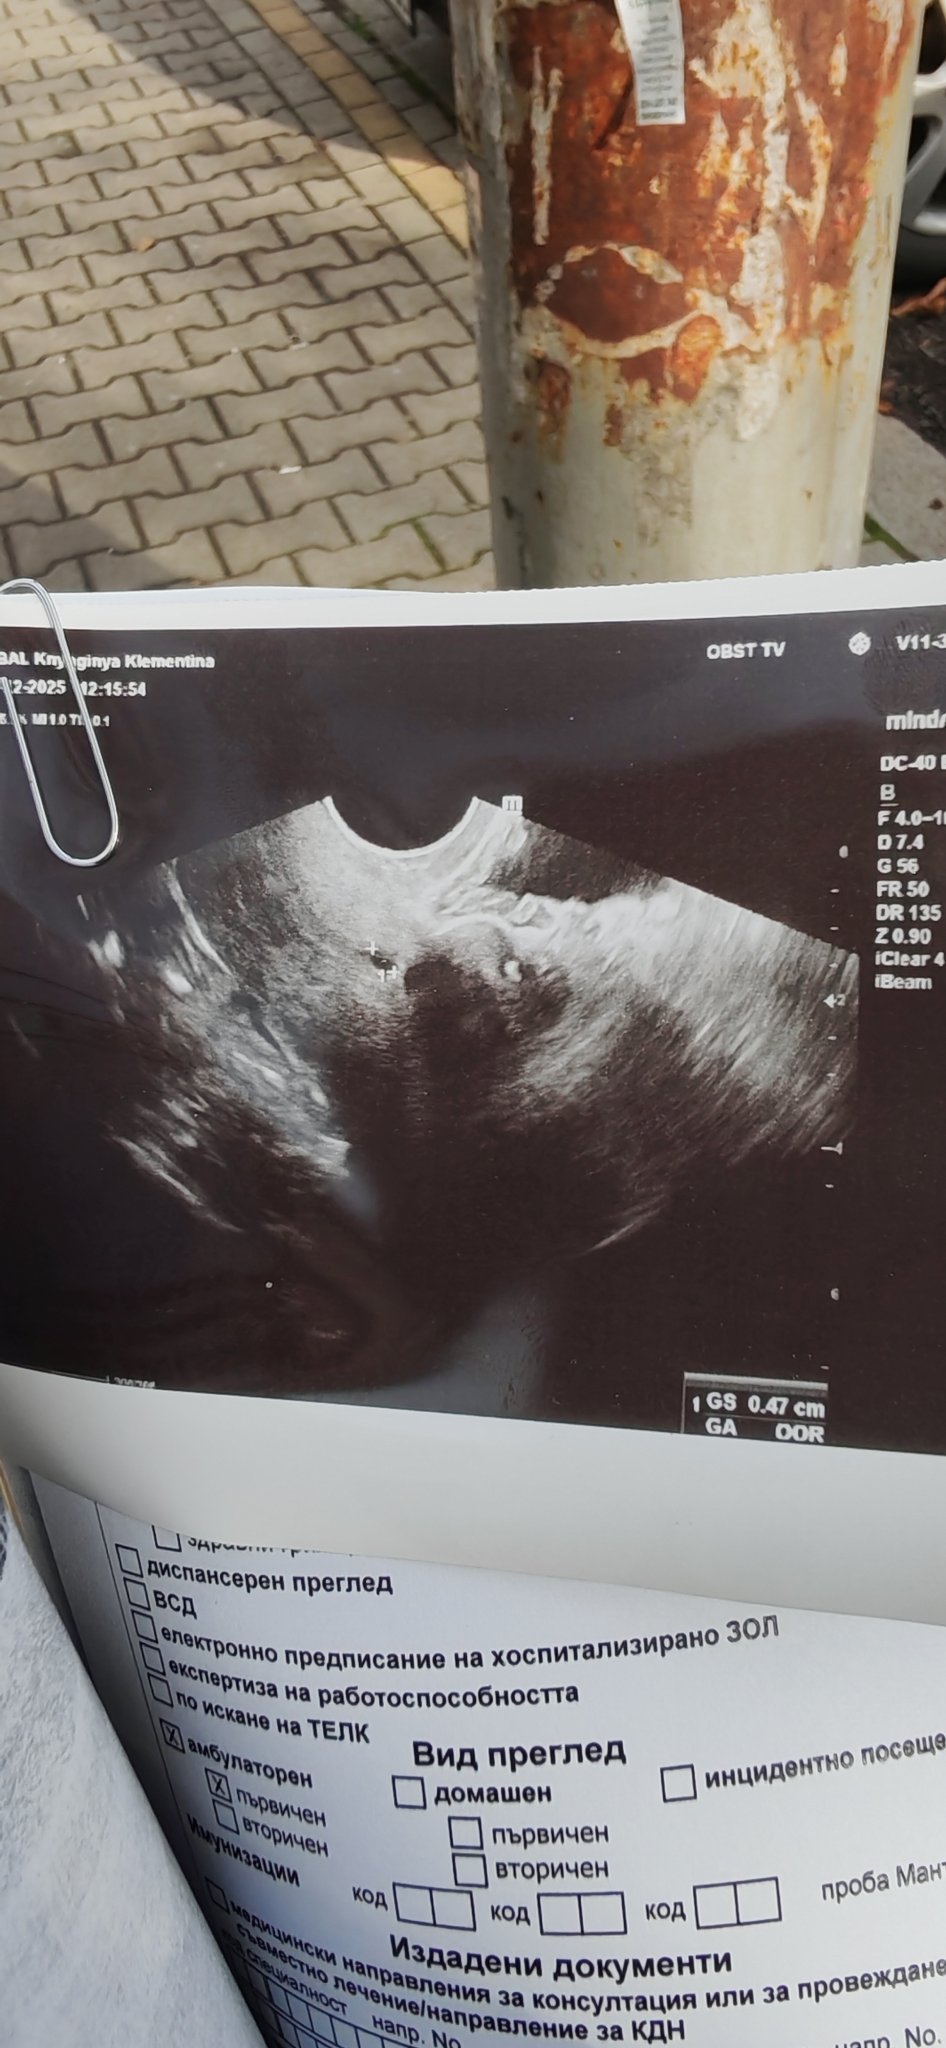

Честно казано изобщо не виждам плодно сакче. На мен прилича на киста на шийката на матката. Ако имате предвид маркирано с кръстове.

Да, това имам в предвид

Отбелязан е плоден сак с размер 0.47 cm. Предвид размера, който е много малък, това вероятно съответства на 4-5 гестационна седмица.